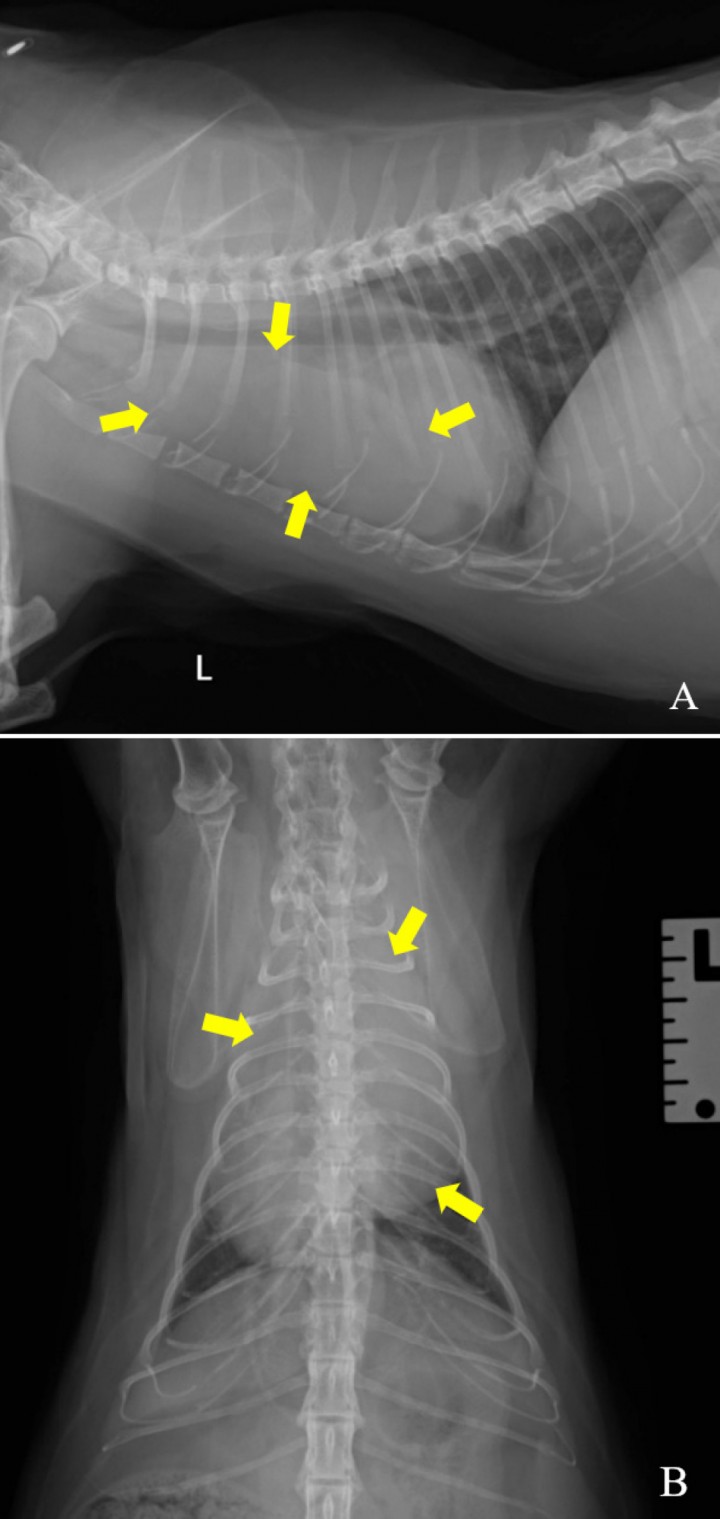

Se aprecia una lesión de opacidad tejido blando situada en la zona craneoventral del tórax (Fig. 2). Esta es de gran tamaño y ocupa gran parte del hemitórax izquierdo. No se pueden delimitar correctamente los márgenes de dicha estructura por presencia de la silueta cardíaca. Esta lesión produce un efecto masa con desplazamiento del corazón dorsocaudalmente y hacia el lado derecho, así como desplazamiento de la tráquea dorsalmente y de la carina dorsocaudalmente.

<p>Radiografías de la Figura 1. Se aprecia una lesión en el mediastino craneoventral que produce un efecto masa (flechas amarillas). L: izquierda.</p>

Radiografías de la Figura 1. Se aprecia una lesión en el mediastino craneoventral que produce un efecto masa (flechas amarillas). L: izquierda.